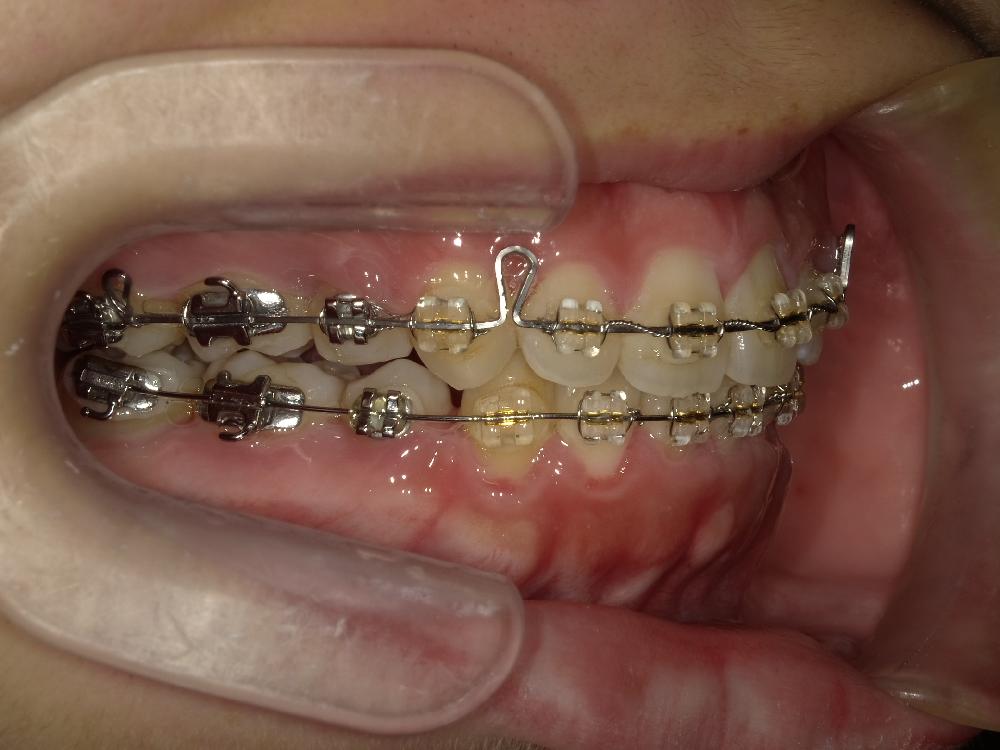

治療中正面

治療中左側

右側治療中